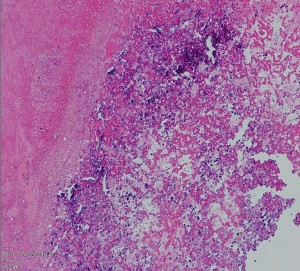

病理所見です

古い用語で凝固壊死 coagulation necrosisという言葉がもっとも適切に病理像を表しています。放射線による血管内皮のダメージで血管壁がヒアリン化して閉塞して虚血となります。また乏突起膠細胞がダメージをうけて髄鞘が脱落します(脱髄)。その結果,炎症と組織修復のための新生血管増殖が生じて脳間質組織浮腫が生じます。IL-1, TNF, IL-6などの炎症惹起性サイトカインはステロイドで抑えられます。同時に,この過程ではreactive astrocytesから多量のVEGFが産生されこれが放射線壊死による脳障害の主因と考えられています。VEGFは血管透過性 vascular permiabilityを増大させるので,組織間浮腫が高度なります。

左,壊死像と脳の境界領域。右,壊死層の中の大小の血管の閉塞像とマクロファージの浸潤がみられます。動脈壁のヒアリン化 hyaline thickening/hyalinizationと血管内腔の閉塞も特徴的な所見です。脳組織は中心部で虚血壊死になり,周囲組織での神経細胞のアポトーシスや白質変性も同時に進行します。この様な部位からの組織低酸素状態で誘発されるVEGFの産生と炎症惹起物質(TNF-alphaなどのサイトカイン)が,細血管からの血漿成分の漏出をまねき脳組織浮腫や慢性炎症を引き起こすと考えられています。fibrinoid deposition, fibrogliosisや微小石灰化の所見を伴うこともあります。

周囲の正常構造を保っている周囲脳組織内の反応性グリア細胞,豊富な好酸性胞体を有するreactive astrocyte(左下の赤い細胞)が多数見られます。 血管新生が盛んに生じていて拡張した毛細血管のような血管構造 telangiectasisが増加します。

放射線壊死の活動期は半年から2年くらいです。その後には脳壊死の部分が萎縮し周囲の脳浮腫は消褪します。組織学的には壊死巣は瘢痕組織となります。中心部は肉芽腫となり周囲にはgliofibrosisを残します。